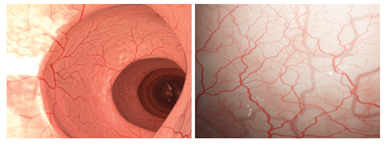

Figure 4. Results taken from [9] showing rendered images of a colon and eye with vessel trees synthesized by their method in under a second.

Following this train of thought, in [11] Martin J. Menten et al. developed a space filling based algorithm for the synthetic generation of Optical Coherence Tomography Angiographies (OCTA). OCT images are crucial for the diagnosis of ocular diseases that manifest as changes in the vessels of the retina. With recent advances in deep learning, semantic segmentations of such images could help ophthalmologists diagnose these diseases much more efficiently.

Similar to the method proposed in [9], the cited authors once again represent vasculature as a directed graph of nodes and edges which is grown iteratively. The construction of the vascular trees is guided by concentration maps of oxygen and endothelial growth factors (VEGF) calculated at each step. VEGF-rich regions are related to low perfusion and in order to supply oxygen to these hypoxic regions, new vessels are developed.

The inner retina is supplied by 4 vascular plexuses, which can be grouped into the superior vascular complex (SVC) and the deep vascular complex (DVC). In order to create vascular trees that mimic real OCTA images, they first generate the SVC with vessel stumps distributed at the edges of the retina, which will later grow towards the center. Once this is done they implement the DVC as smaller vessels which penetrate deeper into the tissue and originate from the SVC. Lastly, they enforce regions with low VEGF to stop angiogenesis at the center of the retina (foveal avascular zone) and the outer retina layers.

In order to train AI algorithms using these synthetic images, they first need to be similar to real OCTA images. To this end, once the 3D geometry has been generated, they apply several processing techniques to obtain 2D grayscale images containing the most common OCT physics-based artifacts.

Figure 5. Synthetically generated retinal graphs [11]